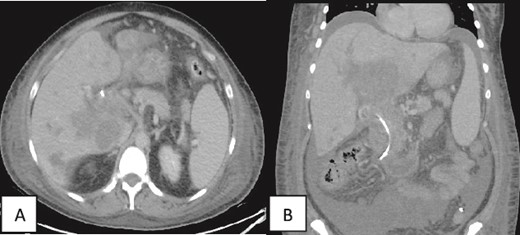

A contrast-enhanced CT scan of the abdomen and pelvis was done and revealed a dilated non-opacified main portal vein and superior mesenteric vein suggestive of thrombosis with periportal vascular congestion as well as a hypo-vascular geographic area with complex fluid density at the hilum of the liver and gallbladder fossa with dilated right and left hepatic biliary ducts. It also showed mild splenomegaly, colonic diverticulosis, and mild ascites mainly in the right iliac fossa. The splenic vein appeared normal, and there were no imaging features of bowel ischemia (Fig. 1).

Contrast-enhanced CT scan of the abdomen and pelvis in (A) axial and (B, C) coronal sections obtained at the porto-venous phase showing a hypo-vascular geographic area with complex fluid density at the hilum of the liver with intrahepatic biliary dilatation. Non-opacification of the main portal vein with early cavernous transformation was noted as well as mild splenomegaly and ascites.